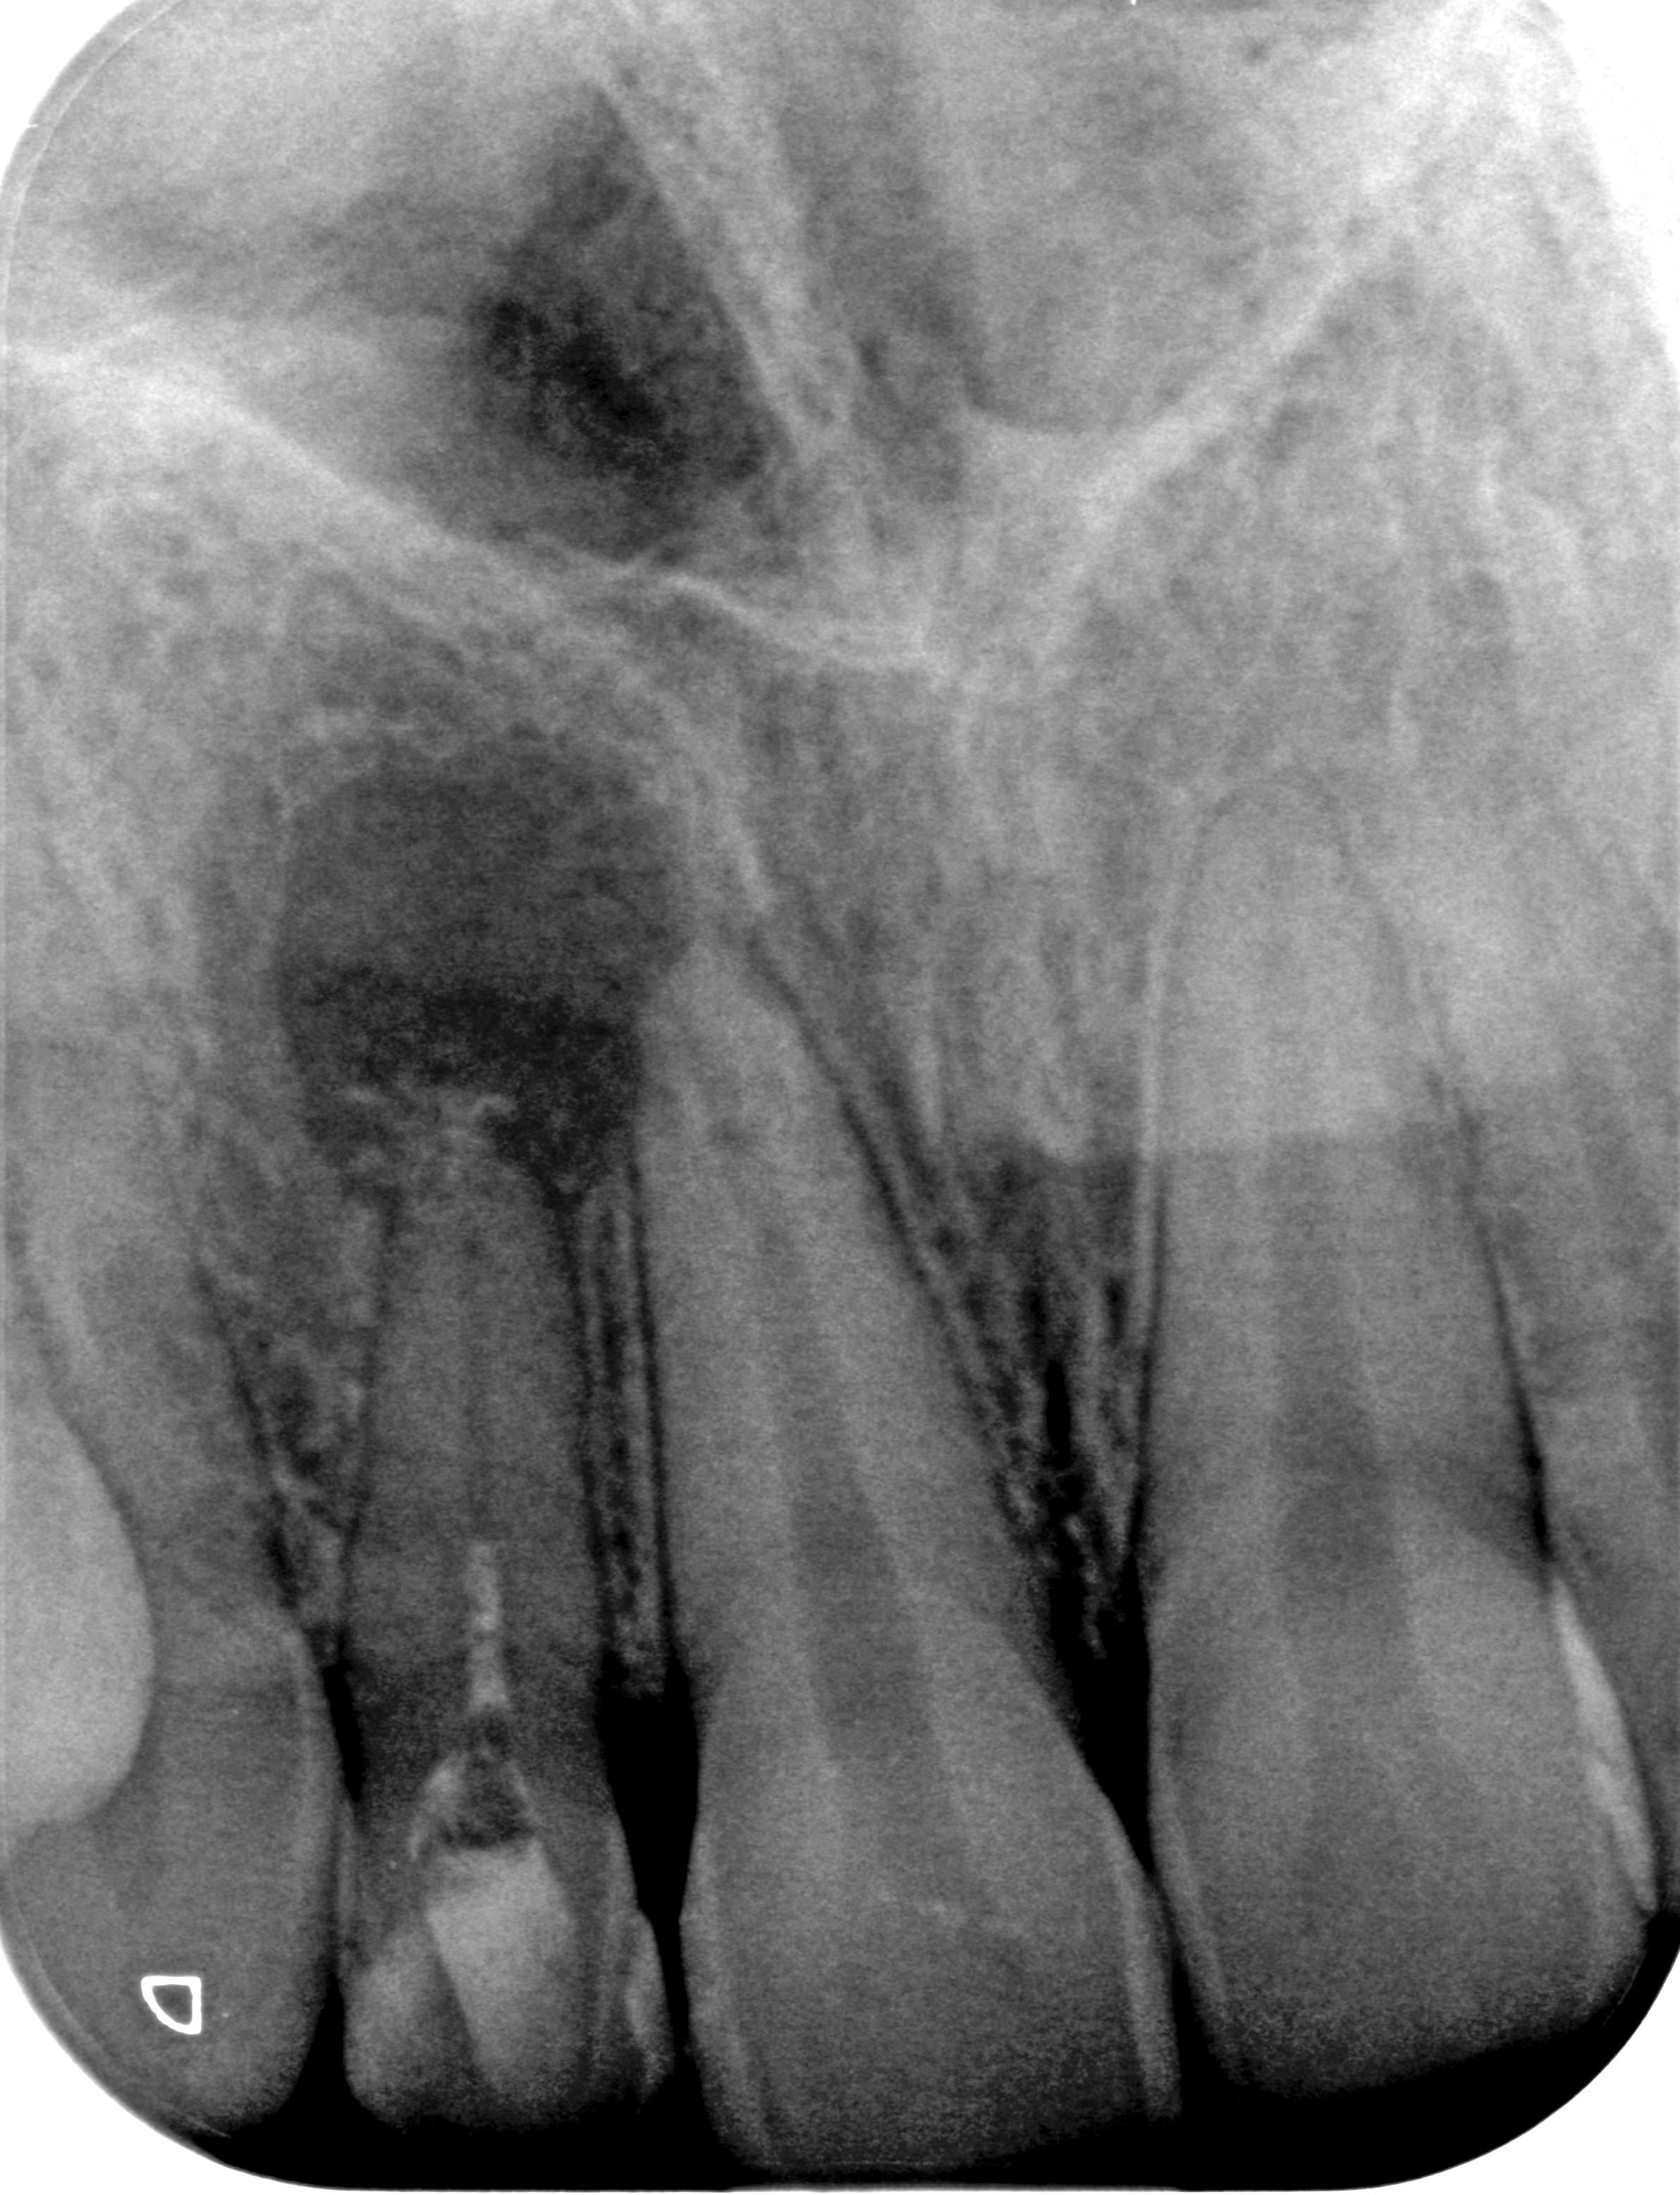

BL_12-1 Veröffentlicht 16. Dezember 2014 am 2383 × 3113 in Die eine geht, die andere kommt… (I) Zahn 12 vor Behandlungsbeginn